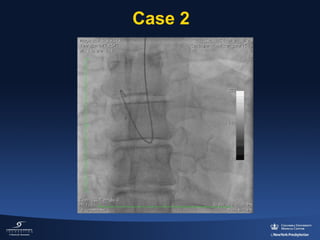

Case 2

•

52 yo M

No past medical history

New onset chest pain 2 am watching TV

Presented at ER 2 hour after beginning of

symptoms

• 250 pounds

• ST elevation in inferior wall

• ASA 80 mg / Ticagrelor 180 mg / Heparin

5,000 U